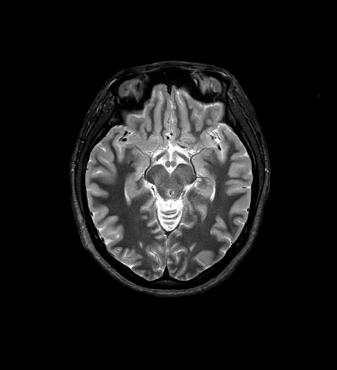

Fig 1: Next generation MRI is being used to gather data on brain tissue volumes Dr. Steve McNally

From this season at Manchester United Football Club, we have started to gather data by using MRI (see fig 1) to measure volumes of brain tissue in specific areas, to monitor for a decrease in volumes over time. If the volumes become unusual or deviate from the norms that we would expect, it may help us identify early changes of CTE that need closer monitoring. This is a new, long-term data gathering study in our cohort of players that has been facilitated with the new next generation MRI3 now in place at our medical centre.